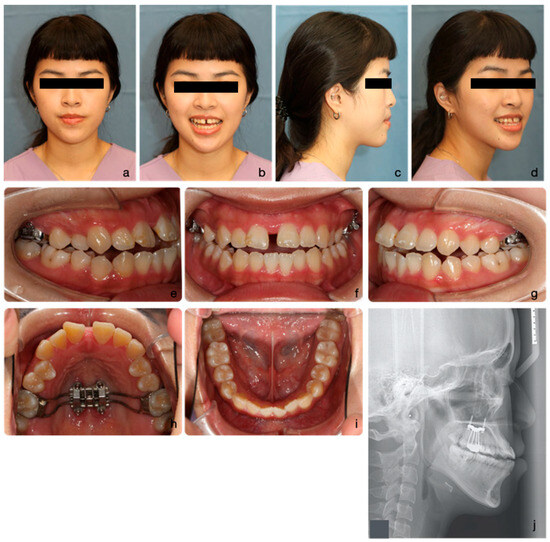

2.4. Treatment Progress

2.5. Treatment Results